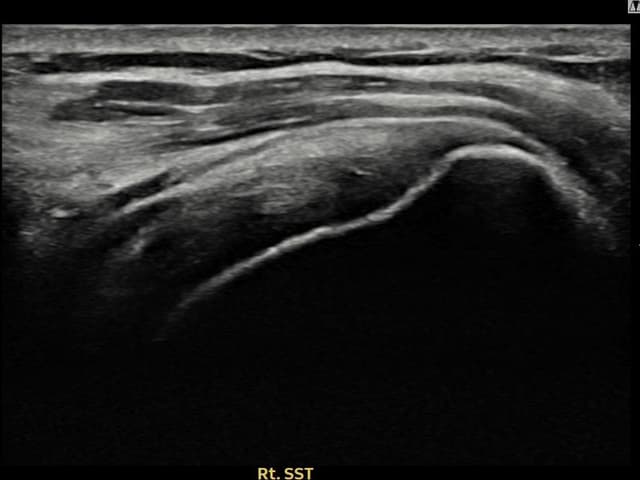

[촬영시기:21.11.15~21.12.02]

[석회분쇄흡입술] 우측 어깨 극심한 야간 통증으로 수면을 이루기 어려웠던 50대 여성 환자로, X-ray에서 극상근건 내 다량의 석회 침착이 확인되어 석회분쇄흡입술을 시행하였습니다.